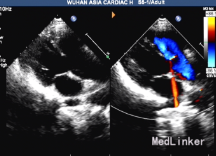

内脏、心房正位,心脏于左前胸探及,心尖指向左下。肝脏位于右上腹,肝静脉、下腔静脉回流入右心房,脾、胃位于左上腹,肺静脉回流入左心房。心室右袢,房室连接一致,二尖瓣、左室位于左侧与左房连接,三尖瓣、右室位于右侧与右房连接。主动脉增宽,前移骑跨于室间隔之上,骑跨率约50%。右室流出道内径为0.8厘米,肺动脉瓣环径为1.4厘米,主肺动脉内径1.8厘米,左右肺动脉分支内径分别为1.0厘米、1.1厘米,肺动脉瓣增厚、回声增强,收缩期右室流出道至肺动脉腔内血流速度增快,峰值速度为5.2米/秒,压差108毫米汞柱。大动脉水平未见明显分流信号。右位主动脉弓。主动脉瓣下室间隔回声连续中断,缺损径:2.1厘米,左室和右室血流射入主动脉。房间隔回声连续完整。右房、右室饱满,左房、左室不大。左室舒张末期容积(EDV)45毫升。二、三尖瓣回声活动正常。